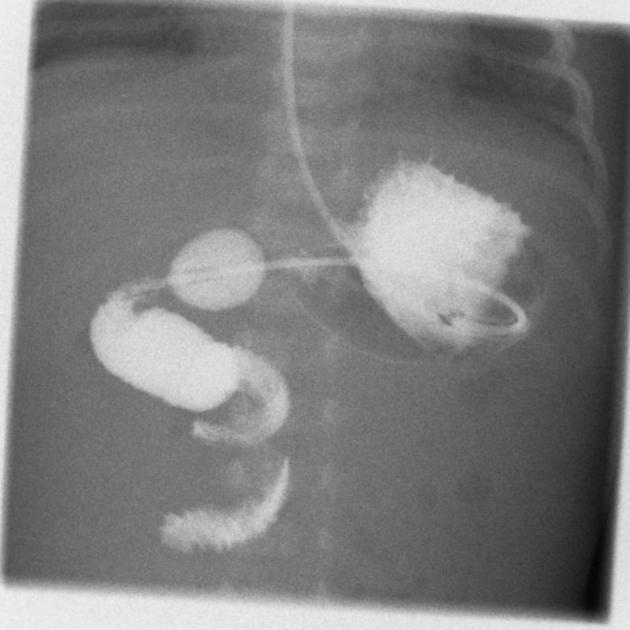

lavement eau sous scopie = 1 m de pression

lavement eau sous scopie = 1 m de pression

= 90% réussite mais 2% perfo et 20% récidive